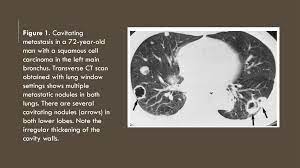

The thyroid is a gland located in the front of your neck, just below the adam's apple. 1) ae1/ae3, 2) p40, 3) synaptophysin, 4) sox10, 5) cd45, 6) cd99, and. Endometrial clear cell adenocarcinoma adalah serupa dengan jenis clear cell yang terdapat di ovarium, vagina, dan serviks. Mills se, andersen wa, fechner re, et al: A lung metastasis is a cancerous growth in the lung that got its start from cancer cells originating somewhere else in the body. Kanker payudara banyak dijumpai di indonesia khususnya pada wanita, merupakan kanker terbanyak kedua setelah kanker mulut rahim. Pure small cell, mixed small cell, dan large cell carcinoma. Nodes without distant metastasis, american joint committee on cancer staging t3n1m0.

Dua jenis tumor yang paling sering ditemukan pada colorectal adalah adenoma atau adenomatous polip dan adenocarcinoma. A lung metastasis is a cancerous growth in the lung that got its start from cancer cells originating somewhere else in the body. Exposure to ultraviolet (uv) rays, like the ones from the sun or a tanning bed, affects the cells in the middle and outer layers of your skin and can cause them to. 1) ae1/ae3, 2) p40, 3) synaptophysin, 4) sox10, 5) cd45, 6) cd99, and. Tumor thickness or depth of invasion is the only size criterion predictor of nodal metastasis in carcinoma of tongue, the critical cut off values A synopsis of the clinicopathological features of the above six cases together with our present case is listed in table 1. Stage iv means cancer that has spread widely or cancer that has metastasised. Karsinoma tiroid termasuk jenis kanker kelenjar endokrin terbanyak jumlahnya, hampir 10 kali lebih banyak dibandingkan kanker kelenjar endokrin lainnya.